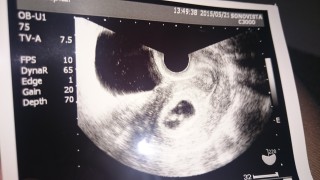

凝視しましたが、「ほら動いてるの見えますか?」と言われて初めて動いてるんだ…と認識しました。右下の写真が心拍の振動です。あまり笑わないクールな男の先生が笑ってくれました。 胎嚢は16.6ミリ、赤ちゃんは6.4ミリでした。お腹の中にもう一つの心臓が動いているなんて不思議な気分です。